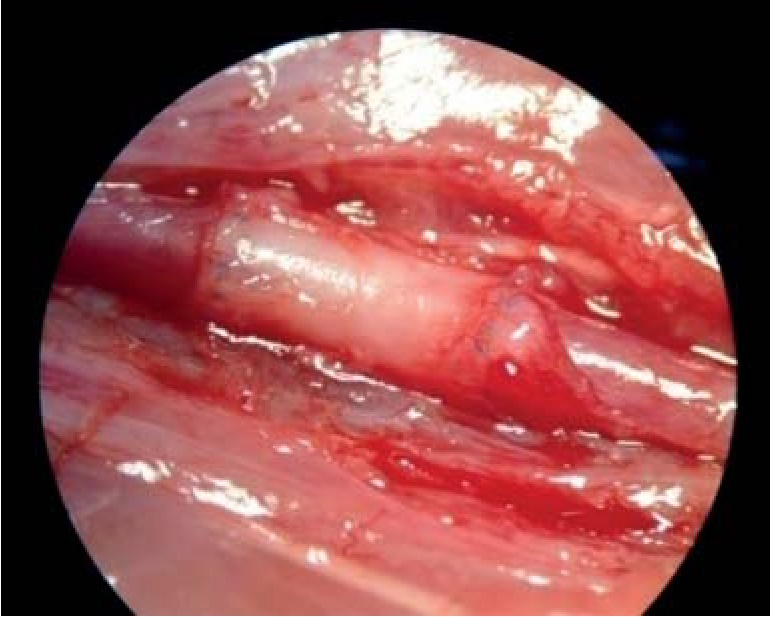

Важная область современной тканевой инженерии – разработка тромборезистентных неиммуногенных протезов кровеносных сосудов, ибо ангиопластика искусственными сосудистыми протезами вследствие их относительной тромборезистентности и биологической несовместимости сопряжена с высоким риском развития тромбозов, воспалительных осложнений и летальных исходов. В научно-исследовательской лаборатории тканевой инженерии НИЦ совместно с Институтом высокомолекулярных соединений РАН, г. Санкт-Петербург разработан двухслойный протез аорты (рис. 5). Совместив в себе позитивные свойства материала биологического и синтетического происхождения, протез обеспечил абсолютную функциональность после трансплантации в инфраренальный отдел аорты крысам в долгосрочном периоде (более двух лет) (рис. 6, 7).

Рис. 6. Внешний вид двухслойного сосудистого протеза через 1 месяц после имплантации

Рис. 7. Двухслойный сосудистый протез через 9 месяцев после имплантации в аорту экспериментального животного (крысы)